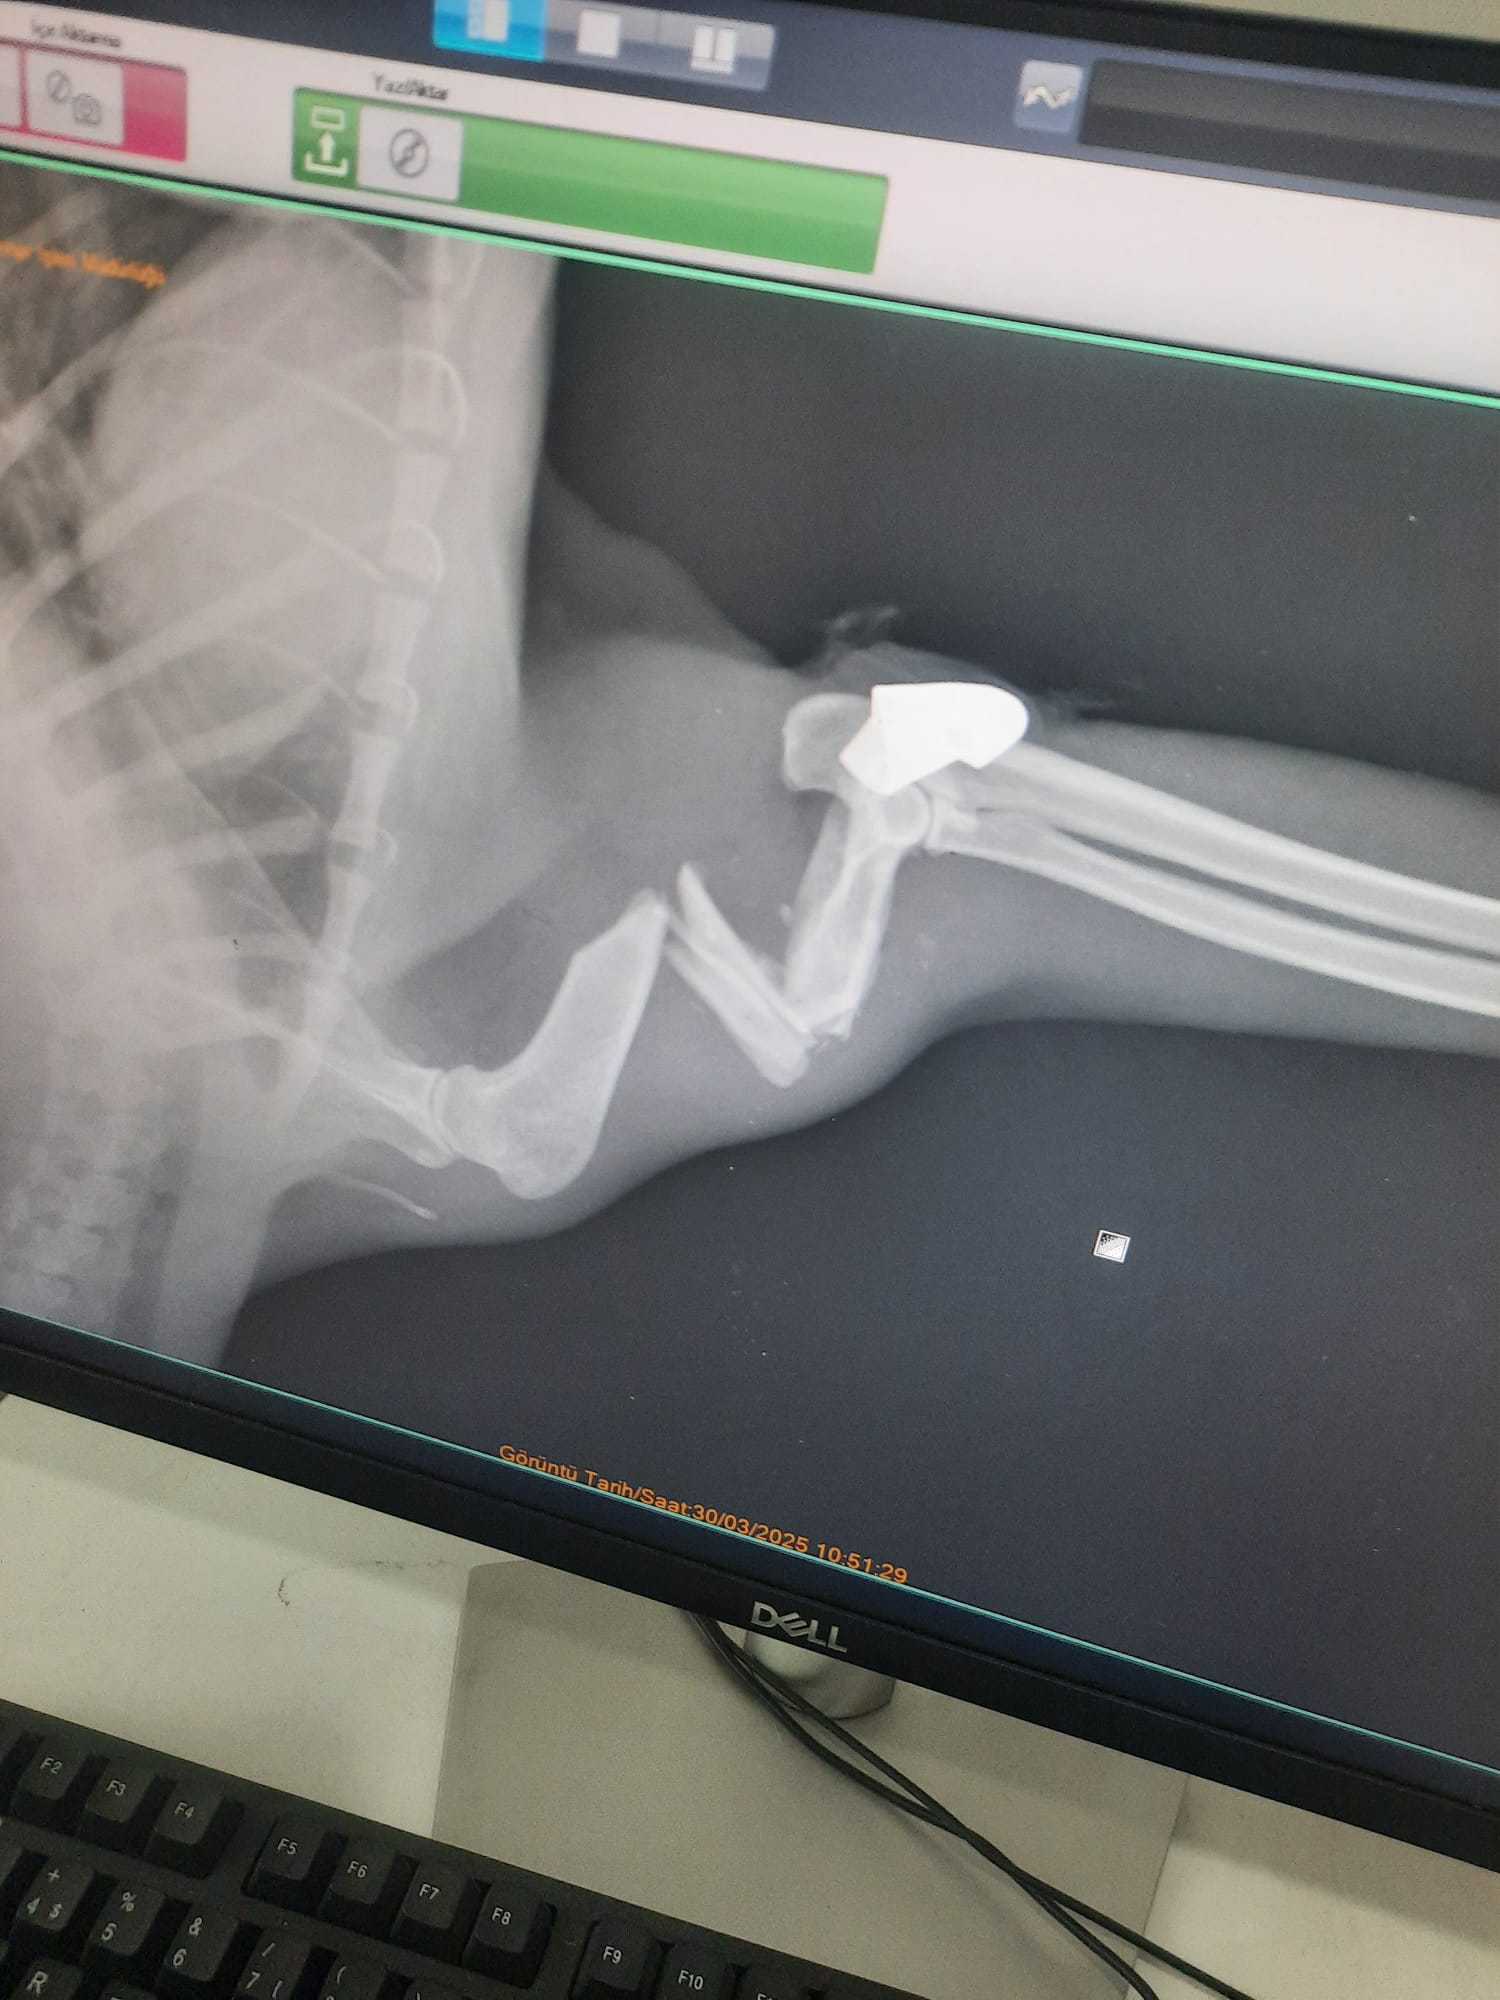

ZONGULDAK'ın Kilimli ilçesinde kaybolduktan 2 ay sonra geri dönen sokak kedisinin patisine mermi isabet ettiği ortaya çıktı. Tedaviye alınan kedinin patisindeki mermi, ameliyatla çıkarıldı.Kilimli ilçesinde, Seda Özkaya'nın baktığı sokak kedisi, yaklaşık 2 ay önce kayboldu. Önceki gün ortaya çıkan kedisinin patisinin üstüne basamadığını fark eden Özkaya, hayvanı tedavisi için Zonguldak Belediyesi Veteriner İşleri Müdürlüğü'ne götürdü. Burada tedaviye alınan kediye röntgen çekilince patisinde mermi olduğu görüldü. Mermi, yapılan ameliyatla çıkarıldı.Zonguldak Belediyesi Veteriner İşleri Müdürü Rıza Akçay, "Röntgenlerini falan çektik. Sonuç olarak, ameliyatını yaptık. Ameliyat başarılı geçti. Eski sağlığına inşallah kavuşacak. Yorgun mermi isabet etmiş. Çekirdeği zaten üzerindeydi. Onun için diyoruz zaten yorgun mermi. Gerekeni yaptık" dedi.'SAĞLIĞINA KAVUŞTU'Seda Özkaya, "Kapıda bakıyorduk. 4 senedir bakıyorduk. 1,5- 2 aydır yoktu. 'Herhalde öldü' dedik. 2 gün önce diğer kedime yemek verirken bir baktım ki, bu geldi. Sevindim ama kolunun üstüne basamıyordu. Biz de 'herhalde kırık' dedik. Buraya geldik, baktık ki kurşun çıktı. Kırık, kemiği çıktı zannettik ama kurşun isabet etmiş. O şekilde tedavisi yapıldı. Şimdi biz bakacağız, çatımızda bakacağız. Çatıya yer ayarladık ona. Sağlığına kavuştu çok şükür. 15 gün sonra kontrole geleceğiz, inşallah. Yorgun mermiymiş, hiç öyle bir şey tahmin etmedik. Ama bizim mahallede zaten insanlar havaya atıyor. Saat kaç olursa olsun fark etmiyor. Büyük ihtimal onlardan isabet etti. Bunlara da bir tedbir gelmesi lazım bence" diye konuştu.